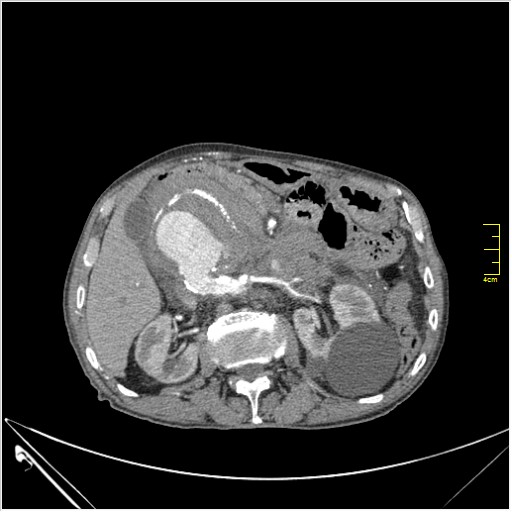

Пациент Т. 64 года, обратился на КТ брюшной полости амбулаторно (!), по направлению семейного врача с диагнозом abdominal mass, буквально: образование брюшной полости.

ИМХО простые кисты.Uzgraph писал(а):Случай интересный - ногу сломишь. Вроде бы анефризма брюшной аорты(особенно по УЗИ), но что тогда за образования сидят на левой почке - онкология?

Huge abdominal aorta aneurism. Simple renal cortical cysts (Bosniak type 1).